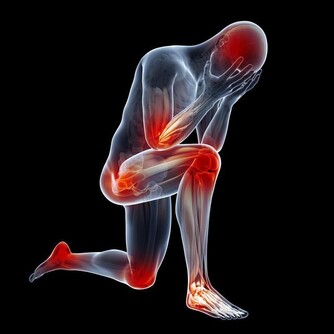

便秘、肥胖、高血壓、糖尿病、脂肪肝、肝炎、痛風、更年期障礙等症狀也有所改善。